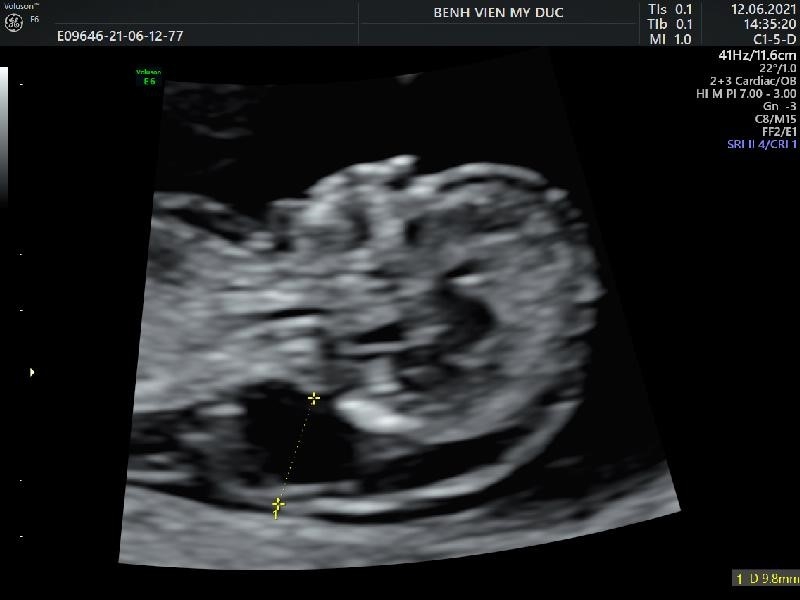

- Patient 28 years old, PARA 0000 – Natural pregnancy.

- Ultrasound at 22 weeks recorded: big tongue, 2 big kidneys, thick placenta, big baby.

Image: thick placenta, large tongue, large kidneys on ultrasound.